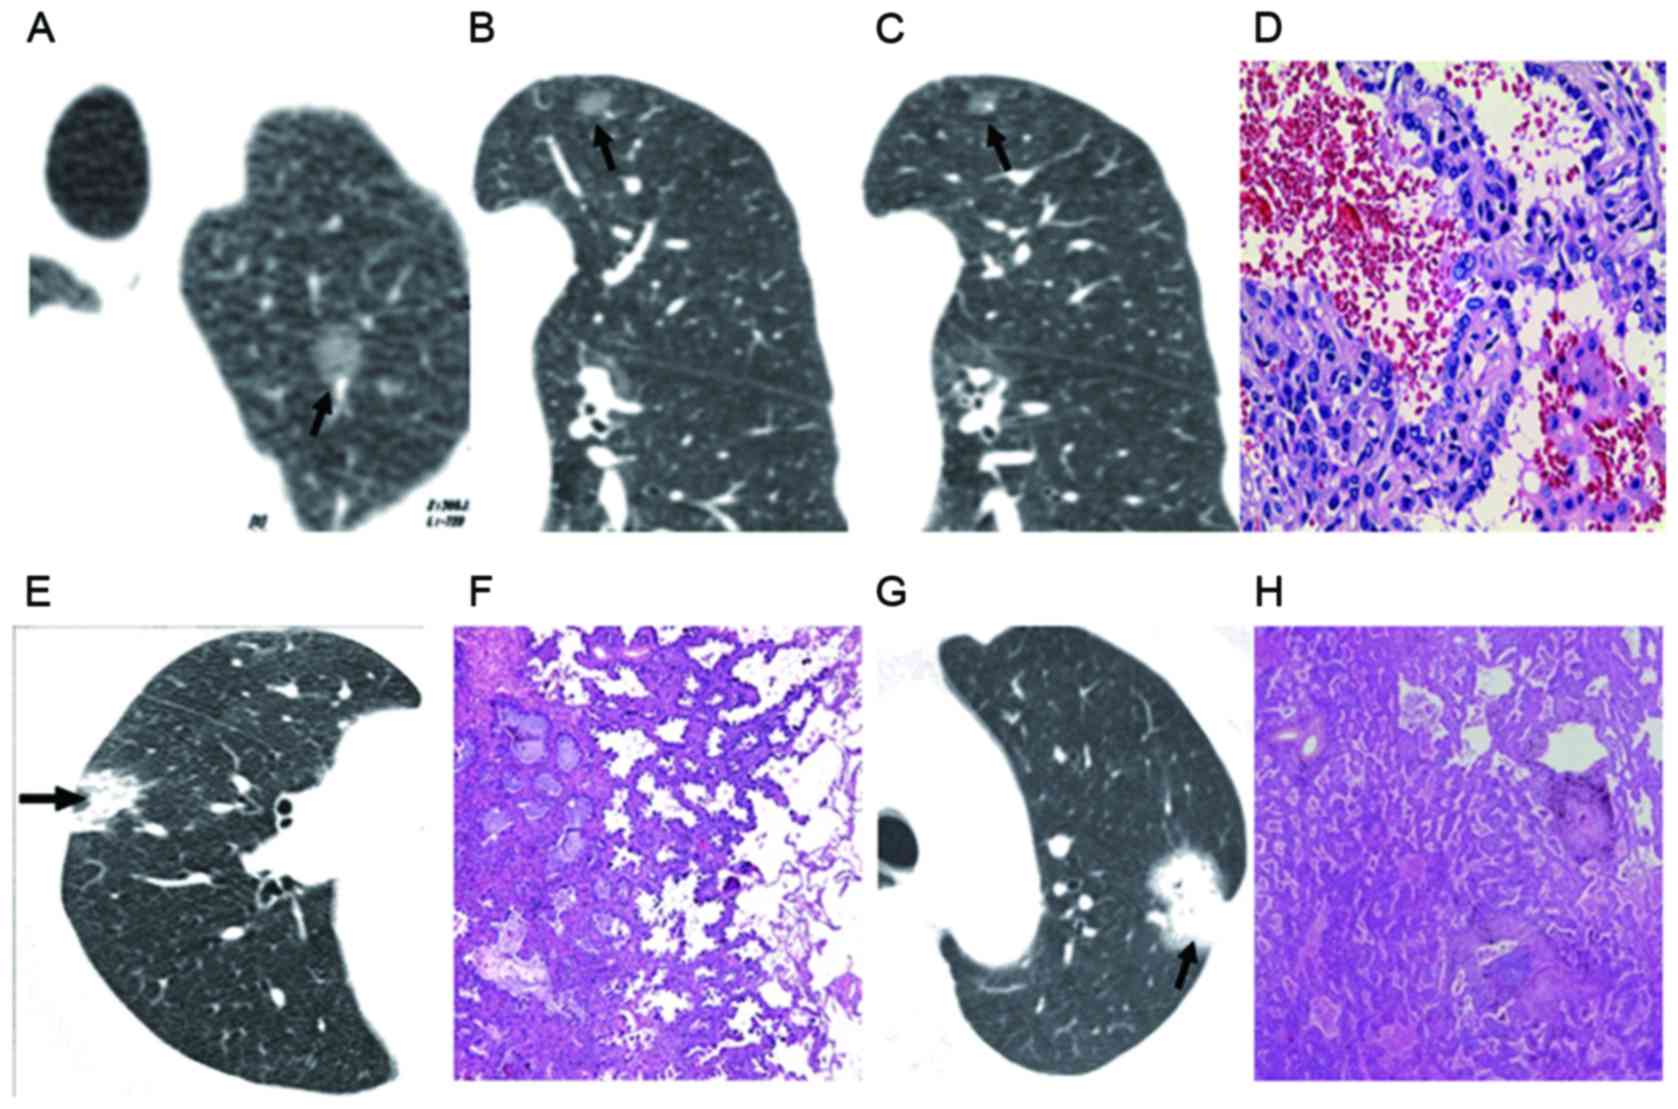

To determine the association between GGO and its pathology, GGO was categorized into four types according to CT scans: Type I is simple GGO (47 cases, as in Fig. 2A-D); type II is uneven density GGO (34 cases, as in Fig. 2E and F), type III is central high density with peripheral burring GGO (19 cases) and type IV is nodule GGO (17 cases, as in Fig. 2G and H). Pathology of type IV GGO revealed the tumor was solid, with no air filling, proliferation of elastic fibers and interrupted or destroyed reticular structure in the tumor. The CT findings, pathology results and statistical analysis are shown in Table II. The malignancy ratio was 68.0% in GGO type I, 61.7% in type II, 73.6% in type III and 70.5% in type IV. As shown in Table II, the malignancy ratio in GGO types III and IV was higher than that in types I and II. This finding suggested that CT scan is of clinical importance in the diagnosis of GGO.

In the current paper, focal GGO was divided into four types based on CT characteristics. There were 47 cases of type I, presenting as clear boundary with leaf edges or burring on CT. There were 11 cases (all type I) of peripheral GGO, with lesions below visceral pleura and away from the vascular bundle. Their pathology showed tumor cells grew along the alveolar wall with no alveolar collapse and mild hyperplasia of elastic fibers in tumor. Of the 47 cases of simple GGO, 12 cases were BAC. There were 34 cases of type II, presenting as uneven GGO on CT. Pathology showed that tumor cells grew along the alveolar wall, with scattered alveolar collapse, severe hyperplasia of elastic fibers and complete network structure within the tumor. There were 19 cases of type III, presenting as central high-density and peripheral GGO on CT. Pathology showed alveolar collapse, proliferation of elastic fibers in tumor center, fractured reticular structure of elastic fibers and growth of tumor cells along the wall. There were 17 cases of type IV, presenting as homogeneous soft nodules on CT. Different types of GGO on CT show differences in pathology (12). In the current study, malignance accounted for 68.0% in type I, 61.7% in type II, 73.6% in type III and 70.5% in type IV. The malignance rate in types III and IV was higher than that in types I and II, which showed the clinical importance of the CT evaluation of GGO.